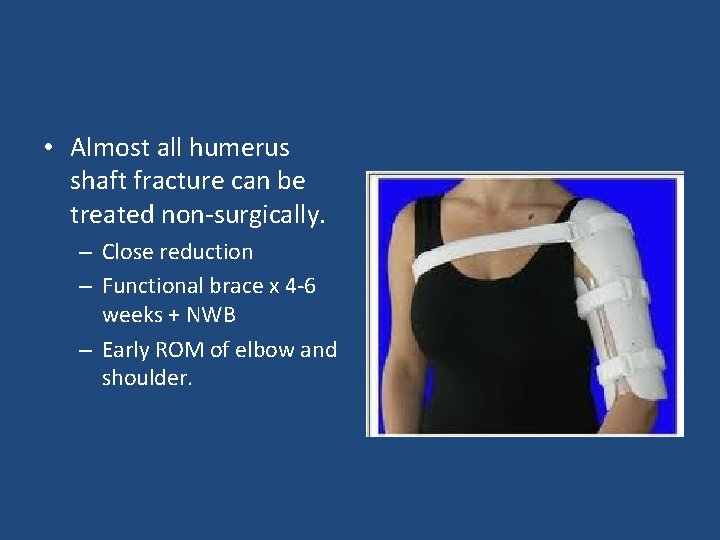

• Almost all humerus shaft fracture can be treated non-surgically. – Close reduction – Functional brace x 4 -6 weeks + NWB – Early ROM of elbow and shoulder.